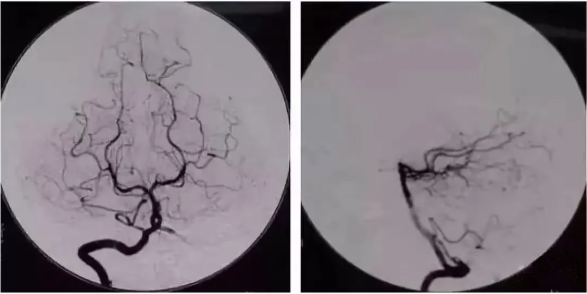

49歲的劉女士因反復(fù)頭暈,多次嘔吐,于8月1日到我院急救醫(yī)學(xué)科就診,行MRI檢查后,初步診斷為左側(cè)小腦半球新鮮腦梗塞、雙側(cè)額葉多發(fā)缺血灶,為進(jìn)一步明確診斷,8月2日醫(yī)院為劉女士進(jìn)行了經(jīng)股動脈置管全腦血管造影術(shù),手術(shù)順利,術(shù)中進(jìn)一步明確了腦血管病變。主管醫(yī)師秦文磊指出,劉女士比較幸運(yùn),左側(cè)椎動脈末端閉塞,遠(yuǎn)端未見顯影,右側(cè)的小腦后下動脈及后交通動脈可向左側(cè)小腦半球代償供血,所以劉女士沒有出現(xiàn)嚴(yán)重的臨床癥狀,術(shù)后可繼續(xù)藥物治療。

經(jīng)股動脈插管全腦血管造影術(shù)是應(yīng)用于臨床的一種嶄新的X線檢查新技術(shù),為神經(jīng)科疾病的檢查、治療提供了新的現(xiàn)代化的手段。它是經(jīng)股動脈超選擇性插管至靶動脈,注入碘對比劑,通過數(shù)字減影對血管進(jìn)行顯象,可清楚顯示頸內(nèi)、外動脈、椎基底動脈以及腦內(nèi)靜脈,為診斷腦血管疾病提供有力證據(jù),特別是對于腦血管狹窄、閉塞、動脈瘤、動靜脈畸形、顱內(nèi)出血等定性定位診斷具有重要的作用。

同時(shí)也是顱內(nèi)血管介入治療技術(shù)的基礎(chǔ),明顯優(yōu)于頸動脈彩超、顱腦CTA、MRA等檢查手段,在臨床中廣泛應(yīng)用,被認(rèn)為是腦血管病變判定的“金標(biāo)準(zhǔn)”。